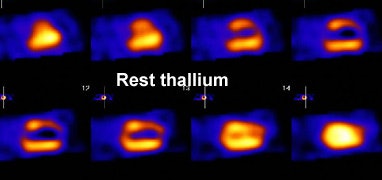

|

Myocardial scar: The patient below was being considered for coronary bypass surgery. A rest thallium exam demonstrated findings consistent with an apical and anterior wall scar. FDG PET imaging was requested to confirm that the patient was not a surgical candidate. The PET scan demonstrated a severe apical and anterior wall metabolic defect with less than 50% of peak myocardial activity corresponding to the thallium scan abnormality. The finding was consistent with prior apical and anterior wall infarct. |

|

|